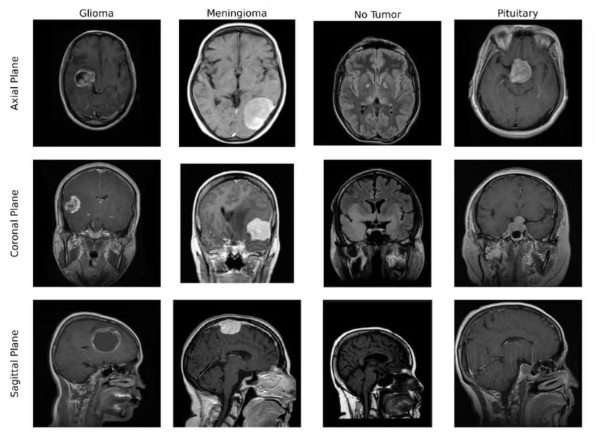

A ferramenta é capaz de fazer a classificação de tumores cerebrais a partir de imagens de ressonância magnética e, no estudo, alcançou uma precisão de 99,75% na identificação de quatro categorias, sendo três tumores – glioma, meningioma, adenoma de hipófise – e cérebro saudável.

“Essas imagens não tem o corte do mesmo jeito, na mesma dimensão, às vezes é horizontal, às vezes é vertical, então a gente tem vários tipos de corte do cérebro para poder fazer esse tipo de análise. Então, dessas 1.300 que a gente fez, essa rede errou só um”, disse a professora Ângela Leite Moreno, orientadora do projeto.

“Ao olharmos para algo novo, primeiro percebemos formas simples, como linhas e cores, e, à medida que focamos mais, conseguimos identificar detalhes complexos até reconhecermos o que estamos vendo. Da mesma forma, essas redes analisam imagens de ressonância magnética, começando por características básicas até identificarem padrões específicos que ajudem a distinguir as imagens entre diferentes tipos de tumores cerebrais e cérebros saudáveis”, explica Ferreira.